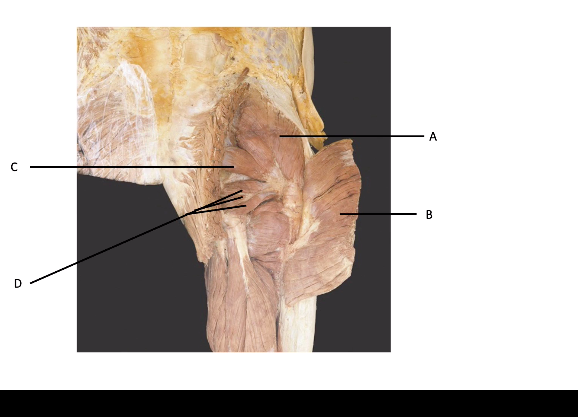

A = gluteus medius B = gluteus maximus C = piriformis D = other lateral rotators